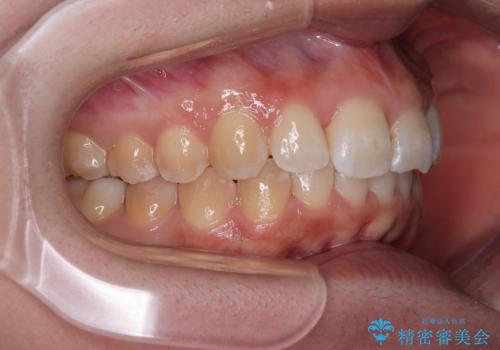

前歯のデコボコをインビザライン矯正で綺麗に改善

- 上下前歯のデコボコを気にして来院された患者様です。

全体的に叢生は軽度であったため、インビザラインにて矯正治療を行うこととしました。

舌の突出癖改善がうまくいかず、途中で舌小帯の切除を行いました。

気になる段差を納得いくまで改善させたため、治療期間は長くなりましたが、綺麗な仕上がりとなりました。